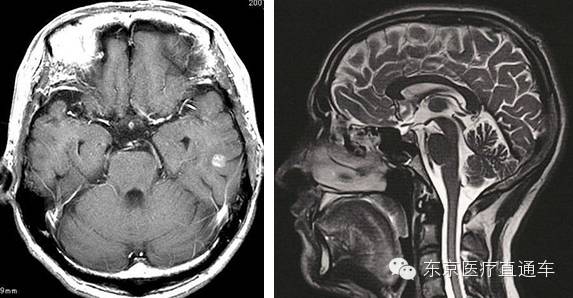

2:脑部核磁共振(MRI)检查

脑部核磁共振(MRI)是在一个有高强度磁场的圆筒型仓体内,使用电磁波对脑部进行立体扫描。检查有无脑肿瘤、脑梗塞等脑部疾病。MRI的检查特点是,能够发现各种脑部早期疾病。

3、脑血管造影(MRA)检查

脑血管造影(MRA)是一种利用磁场力量来检查脑部血管的状态情况。通过检查,不仅可以发现导致蛛网膜下腔出血的脑动脉瘤的疾病隐患,还能够查出是否存在引起脑梗塞的脑部血管狭窄。致力于将任何脑部疾病风险降到最低。